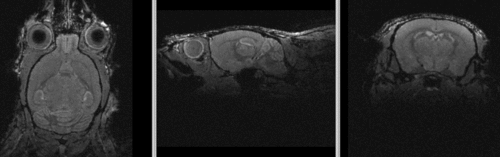

shown are, from left to right, panels of axial, sagittal and coronal views.

original brain in non-RAS orientation original, not RAS

original brain in proper RAS orientation original,after reorientation into RAS